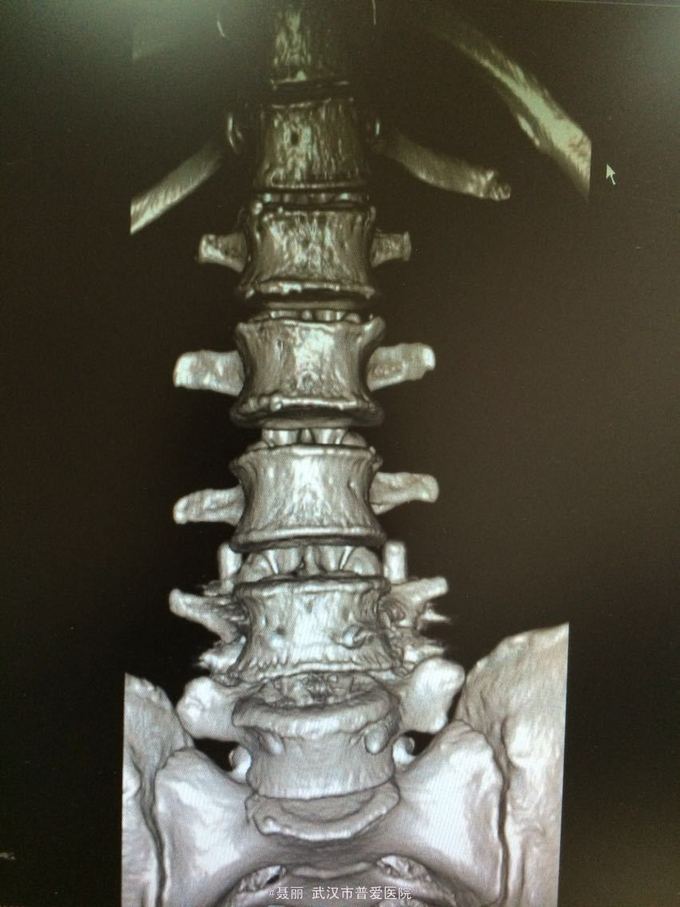

患者,女,61岁 因腰部疼痛,伴左下肢酸胀、疼痛、麻木5月余入院。 患者约5月前无明显外伤等诱因感腰腿疼痛不适,以腰部及左下肢为主,活动后左下肢疼痛加重,休息可缓解。 既往病史:既往体健,否认高血压、糖尿病等其他传染病史,否认食物药物过敏史。

辅助检查:2015年2月27号到我院拍腰椎MRI检查提示:L4椎体Ⅰ-Ⅱ度滑脱,腰椎退变。

初步诊断:腰椎滑脱症 治疗计划:1、完善相关检查:胸片、心电图,血常规,尿常规,肝肾功能电解质、术前全套 2,活血化瘀扩管治疗。卧床休息。 L4滑脱复位+L4/5椎间盘摘除、椎管减压+椎间cage3植骨融合术